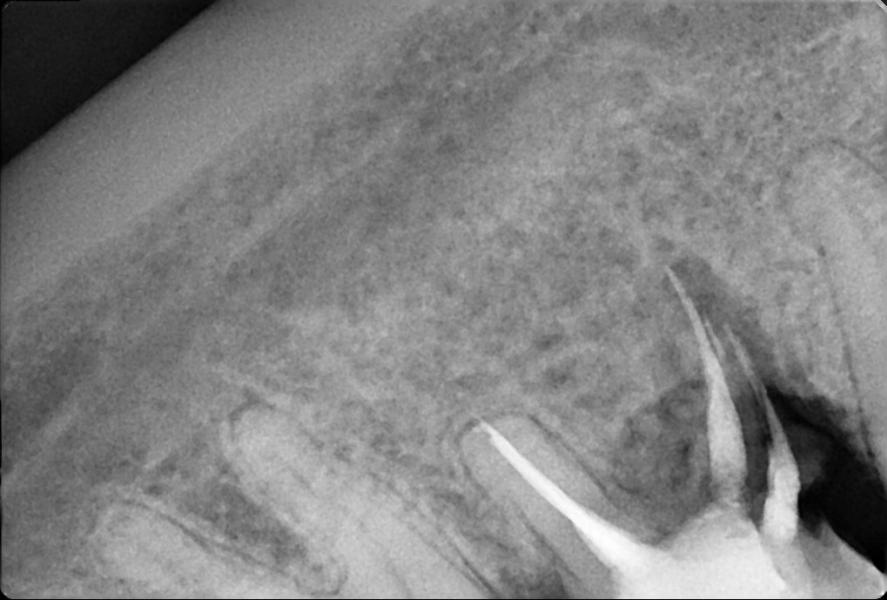

Резорбция корня зуба: у кого было? Что делали, чтобы избежать удаления? Поделитесь опытом!

Кто сталкивался с резорбцией корня зуба? Что делали в вашем случае?Так не хочется удалять😭